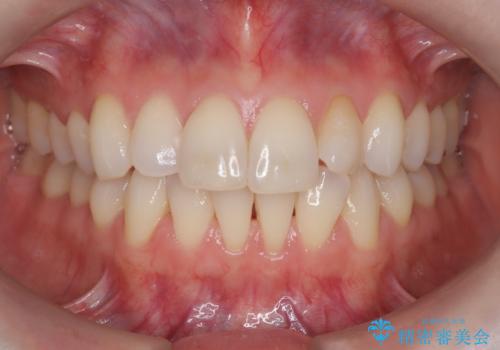

矯正後の後戻りで前歯にガタツキができてしまった インビザラインで改善

- 子どものときにワイヤー矯正をしていたが、後戻りによって前歯のガタツキが気になってきたとのことで来院されました。

アライナー矯正希望だったため、インビザラインによる治療を行いました。